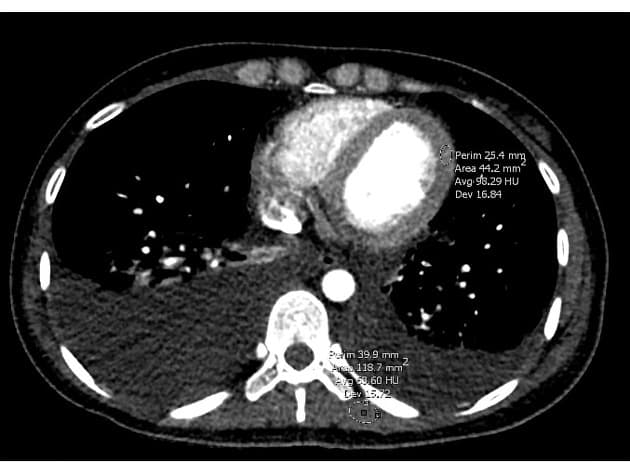

Phân tích hình thái và chức năng (tính toán thể tích nội tâm thất – bao gồm cả cơ cột tì):

- Lưu lượng tim: 7,3 L/phút

- Chỉ số tim: 3,7 L/phút/m²

- Chỉ số khối thành thất trái cuối tâm trương (không bao gồm cơ cột tì): 62 g/cm

- Độ dày vách liên thất: 11 mm

- Vùng co bóp giảm nhẹ, đặc biệt ở các đoạn đáy vách liên thất dưới và thành dưới.

Đặc tính mô cơ tim

- Tăng quang muộn ở vùng dưới ngoại tâm mạc (subepicardial late gadolinium enhancement) tại các đoạn đáy và trung thất dưới.

- Hình ảnh STIR gợi ý phù cơ tim (myocardial edema) ở các đoạn đáy và trung thất vách liên thất dưới, thành dưới và thành bên dưới.

- Bản đồ T1 không tiêm thuốc (native T1): tăng cao, đặc biệt ở thành dưới đáy và trung thất.

- Thể tích ngoại bào (extracellular volume – ECV): tăng (>32%) ở các đoạn đáy thành dưới và bên dưới.

- Bản đồ T2: tăng rất nhẹ (56 ± 10 ms) ở đoạn đáy thành dưới, trong khi giá trị bình thường ở vùng cơ tim xa tổn thương là 48 ± 4 ms.